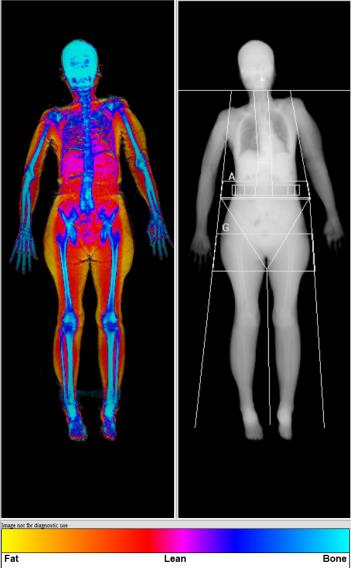

肌少症的檢查方式,可利用雙能量X光掃瞄儀(DXA)、生物電阻分析(BIA)及核磁共振(MRI)和電腦斷層(CT)。生物電阻分析(BIA)是根據測量全身電阻電導率得出肌肉質量的估計值,因數值容易受身體內含水量不同而改變,還是有一定的誤差,但其測量值尚可接受,因簡易、便宜、安全,常用於社區肌少症篩檢。相較之下,DXA為專業醫療儀器,精準度高,目前各醫院仍是以雙能量X光掃瞄儀(DXA)來檢測肌肉量。核磁共振(MRI)和電腦斷層(CT)是非常準確的檢查,但C T的輻射劑量高,M R I 檢查時間長,兩者檢查費用也較高。 亞洲肌少症共識會(Asian Working Group for Sarcopenia, AWGS)對於肌少症評估條件為:利用雙能量X光掃瞄儀(DXA)檢測,前一天建議避免重訓(會導致肌肉受損),並於檢查前排空尿液、移除身上所有飾品,穿著輕便衣褲。掃描時平躺在檢查台上時間約7-8分鐘即可完成檢測。

▎全身身體組成成分分析

雙能量X光掃瞄儀(DXA),可同時檢測全身「骨密度」 及「身體組成成分」。用DXA分析身體組成,誤差會比生物阻抗分析的儀器小,是相對比較精確,又能在臨床上執行的方式。檢查時除了可檢測(1)有無肌少症:肌肉質量的不足易造成肌少症,還可分析(2)內臟脂肪: 內臟脂肪太高會造成三高病變且內臟脂肪會釋放出發炎物質,使腦神經細胞容易受攻擊,增加失智風險,及(3)全身體脂百分比:體脂過高會導致心血管疾病及慢性疾病。一言以蔽之,脂肪過多時,易形成代謝及系統性疾病,進而造成身體羸弱及肌肉質量的急、慢性減少,也不利於健康。所以留意自身身體組成成分是關愛自己的基本步驟之一。

肌少症及代謝症候群高風險族群

81歲女性

身高          142.3cm

體重           39.1kg

體脂率         32.3%

BMI          19.3kg/m2

內臟脂肪VAT  53.3cm2

(正常)

四肢骨骼肌  4.59kg/m2

質量指數ASMI   有肌少症風險

(肌肉質量不足)